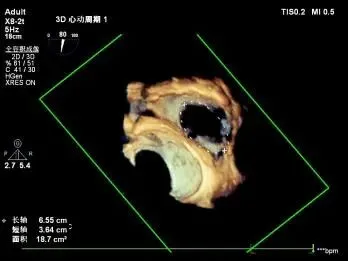

超声心动图:三尖瓣瓣环显著扩张(平均径42mm),瓣叶对合不良,TR 4+;肺动脉收缩压 58mmHg;左心室射血分数(LVEF)54%;人工二尖瓣功能未见异常。

1. 瓣环面积由18.7降至11.9,瓣环面积减少36%。